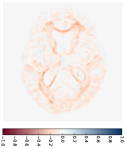

Figure 4 shows the prediction results of our model for one subject sample from the non-demented test group in the OASIS dataset. This subject has MRI scans at 80, 81, 85, and 86 years old, and there are missing images at multiple time points. We predict one image scan per year from 80 years to 88 years, including those missing ones, as shown in the second row of Fig. 4. Since the brain changes are quite subtle (see the first row of Fig. 5), we also plot the deformation map at each time point, as shown in the last row of Fig. 4. These deformation maps show the estimated changes in the brain MRIs. As we can see, the grids are expanding, especially around the brain ventricle region. This expanding ventricle indicates our model captures the degeneration process of the ventricle in the brain, i.e., an enlarging ventricle. Figure 5 shows the image difference between predicted images and their corresponding image scans in the second row. Compared to the first row that shows image difference of follow-up scans with respect to the first one, the prediction difference is relatively smaller, especially around the ventricle region. Table 1 reports the means and standard deviations of the prediction difference for all images in the non-demented and demented groups, which are 5.8616e-41.0703e-4 and 6.1105e-41.9793e-4, respectively.

Apart from the subject-specific image prediction, our model can also estimate a group trajectory by predicting forward and backward image sequences for the atlas (the mean image) built for that group. Figure 6 demonstrates the mean trajectory estimated for the demented group. We first estimate the mean image using the unbiased atlas building algorithm (Joshi et al., 2004). This atlas is our baseline input, and we predict vector momenta forward to generate future image scans. By using the negative vector momenta, we shoot the atlas backward and generate previous image scans. From the predicted images within 25 years (every three years shown in Fig. 6), we can recognize the brain changes, in particular, the enlarging ventricle over the years. The deformation maps shown in the second row are generated starting from the atlas in the middle. Therefore, they show the expanding grids in the forward sub-sequence and the compressed grids in the backward sub-sequence.